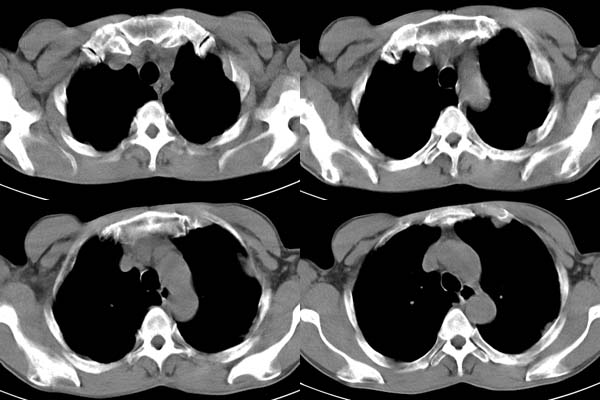

患者,男,65岁,咳嗽,胸痛

说肺癌纵隔窗上不典型,而胸膜间皮瘤却又没胸水。我觉得胸膜间皮瘤放第一位。

ct所见;左下肺可见片状阴影,密度不均,边缘尚清晰,胸膜方向见有条索相连,纵隔窗未见具体结节。左侧胸膜下见多个软组织结节且以宽基底与胸膜相连,右侧胸锁关节层面亦见软组织结节广基与胸膜相连。纵隔未见肿大淋巴结,气管,支气管开口正常。

有没有石绵史?